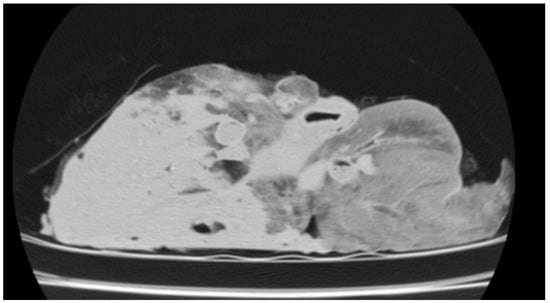

3.3.3. Chronic Form of Ovine Respiratory Complex (ORC)

| GN | Cranioventral lobes, may extend | 20 to 50 HU (walls), 150 to 600 HU (purulent/necrotic content) | Hypodense necrotic tissue; high HU in purulent/putrid areas |